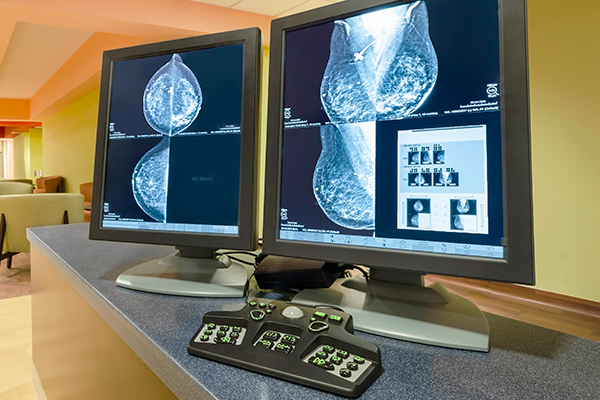

유방촬영검사란?

유방촬영은 유방의 내부 구조를 X선으로 촬영하는 기초 검사로

유방암 검진에 있어 기본이 되는 검사입니다.

종괴 또는 석회화 등을 확인하기 위해 촬영합니다.